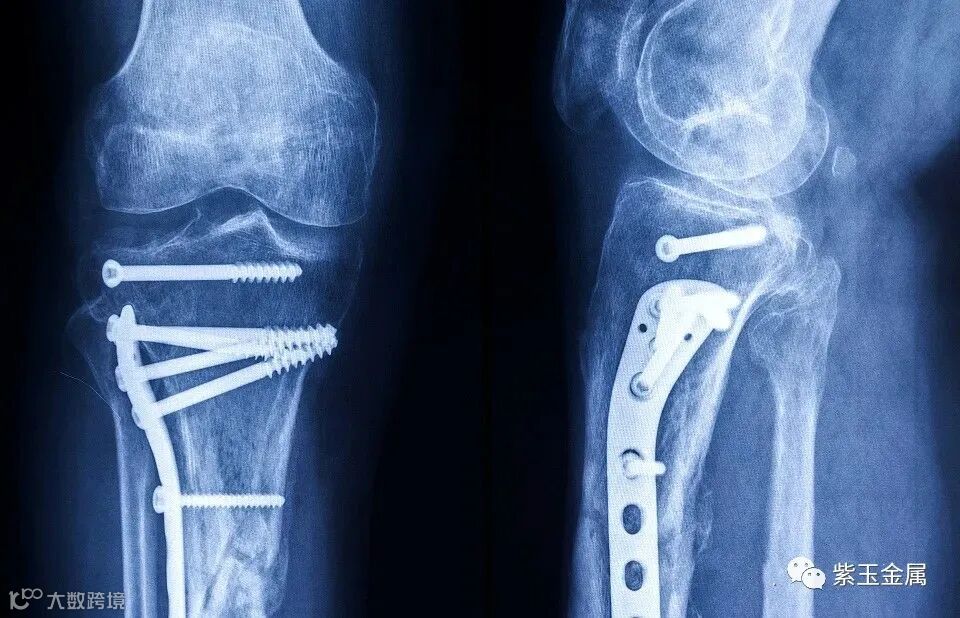

使用钛及钛合金作为人体植入物的优势主要有:(1)密度(20℃)=4.5g/cm3,质轻。植入人体内:减轻人体负荷量,作为医疗器械:减轻医务人员操作负荷。(2)弹性模量低,纯钛为108500MPa,植入人体内:与人体自然骨更接近,利于接骨,减少骨头对植入物的应力屏蔽效应。(3)无磁性,不受电磁场和雷雨天气影响,利于使用后的人体安全。(4)无毒性,作为植入物对人体无毒副作用。(5)抗腐蚀性(生物惰性金属材料),在人体血液的浸泡环境中有优异的耐腐蚀性能,保证与人体血液及细胞组织的相容性好,作为植入物不产生人体污染,不会发生过敏反应,这是钛及钛合金应用的基础条件。(6)强度高、韧性好,因外伤、肿瘤等因素导致骨、关节损害,为建立稳固的骨支架,必须借助弧型板、螺丝钉、人造骨及关节等,这些植入物要长期留置于人体内,会受到人体的弯曲、扭转、挤压、肌肉收缩力等作用,要求植入物具有高的强度和韧性。

生物医用钛及其合金材料的应用经历了3个标志性阶段:应用初期50年代初,首先在英国和美国,商业纯钛被用来制造接骨板、螺钉、髓内钉和髋关节。瑞士Mathys公司也采用Ti-6A1-7Nb合金制造非扩髓带锁髓内钉系统(包括胫骨、肱骨、股骨)及用于治疗股骨颈骨骨折的中空螺钉等。多孔Ni-Ti(PNT)合金生物活性材料制造颈、腰椎间融合器加拿大BIORTHEX公司研制出采用多孔Ni-Ti合金专利材料ACTIPORE伽制造颈、腰椎间融合器用于骨科脊柱损伤的治疗。新型β钛合金可兼顾骨科,齿科和血管介入等多种用途的先进材料骨科医疗器械行业占比全球医疗器械市场份额的9%,且仍处于快速增长中。

骨科医疗器械市场的主要划分为四个领域创伤、关节、脊柱和其他。其中创伤类是目前唯一没有被外企占据主要市场份额的细分领域,主要原因是该领域产品技术含量较低,易仿制,手术难度较小,众多二三级医院都可进行,外企无法全面覆盖。创伤类产品可以分为内固定和外固定器械,内固定创伤类产品包括髓内钉、接骨板和螺钉等,2012年国内骨科市场中创伤占比34%,关节28%,脊柱20%,其他18%。大关节属于高端医疗器械,技术壁垒较高,目前主流医院对骨科材料的选用上都是以进口为主,在技术、设计、研发、材料、表面处理工艺等方面,国产与进口产品还存在差距。